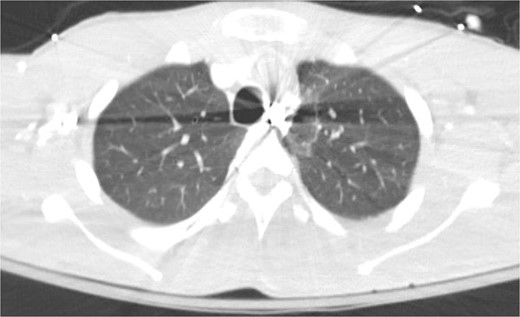

A repeat otolaryngology endoscopy exam on HD 2 revealed a 1.5 cm wound in the posterior pharyngeal wall, confirming the suspicion that the bullet entered the posterior of the mouth, was swallowed, and was now migrating down the GI tract. Serial X-rays tracked its transit (Fig. 4). Despite treatment, his condition remained critical. He underwent tracheostomy, gastrostomy, and diaphragmatic pacemaker placement. The patient was discharged to a long-term care facility on HD 22 but succumbed to complications from AIDS and pneumonia months later.